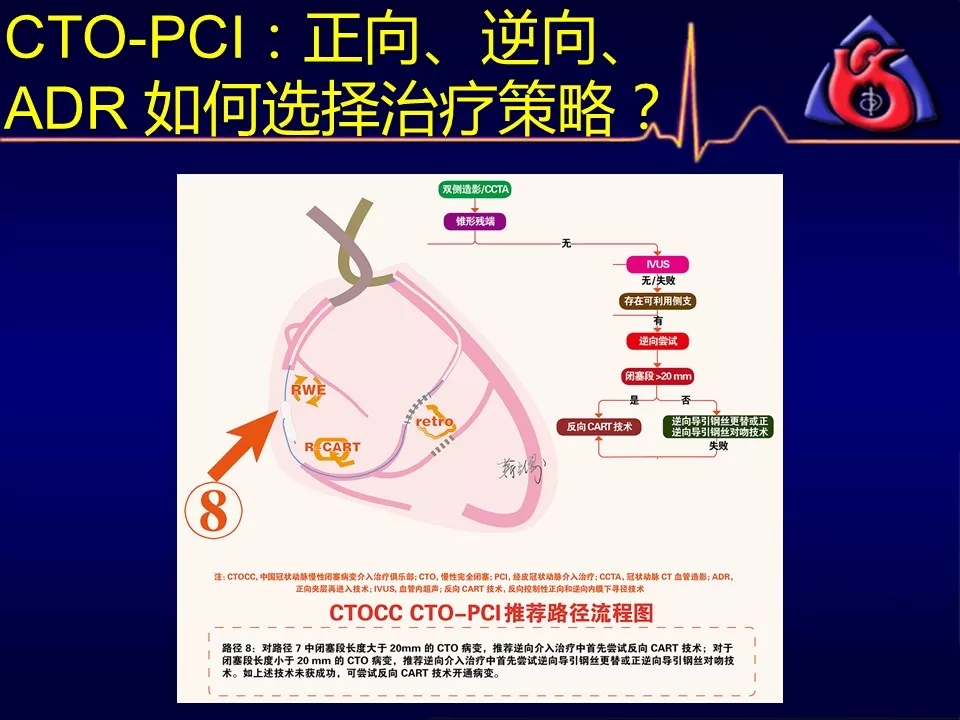

学习CTOCC CTO-PCI流程图的你

一定有此疑惑:

如何选择正向、逆向、IVUS指引及ADR技术?

别着急,葛雷教授带来动态幻灯版讲座:

《CTOCC CTO-PCI流程图精讲》

为您解答上述疑问

PS:本篇为第一部分